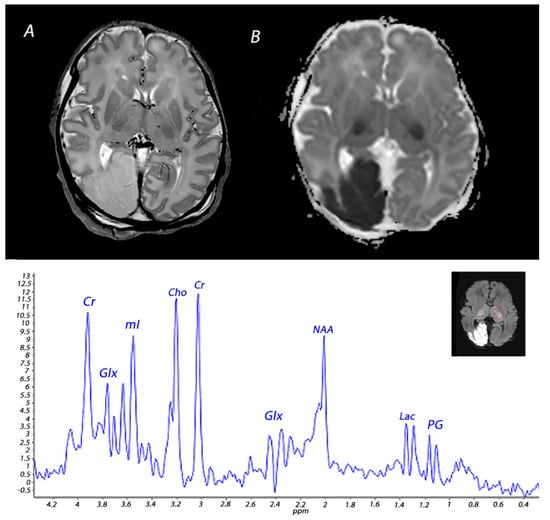

5. Magnetic Resonance Spectroscopy

- Shibasaki, J.; Aida, N.; Morisaki, N.; Tomiyasu, M.; Nishi, Y.; Toyoshima, K. Changes in brain metabolite concentrations after neonatal hypoxic-ischemic encephalopathy. Radiology 2018, 288, 840–848. [Google Scholar] [CrossRef]

- Roelants-Van Rijn, A.M.; Van der Grond, J.; De Vries, L.S.; Groenendaal, F. Value of H-1-MRS using different echo times in neonates with cerebral hypoxia-ischemia. Pediatr. Res. 2001, 49, 356–362. [Google Scholar] [CrossRef]

- Wu, T.W.; Tamrazi, B.; Hsu, K.H.; Ho, E.; Reitman, A.J.; Borzage, M.; Blüml, S.; Wisnowski, J.L. Cerebral lactate concentration in neonatal hypoxic-ischemic encephalopathy: In relation to time, characteristic of injury, and serum lactate concentration. Front. Neurol. 2018, 9, 293. [Google Scholar] [CrossRef] [PubMed]

| DWI | High signal intensity on isotropic DWI with low ADC values in the affected areas. | Abnormalities peak at 3–5 days after the insult. Pseudo-normalization occurs after approximately 11–12 days for infants treated with therapeutic hypothermia, and 6–8 days in non-cooled infants. | |

| 1H-MRS | Increased lactate and decreased NAA in the affected white matter. | Lactate in general increases <24 h and subsequently normalizes by the end of the first week, but persistent elevation has been reported. 1 NAA declines <24 h and remains low during the first 2 weeks after the insult, although some studies have reported that NAA levels do not significantly diminish until approximately 48 h after the insult. 2 | |

| 1H-MRS | Increased lactate and decreased NAA in basal ganglia and thalami. | Lactate in general increases <24 h and subsequently normalizes by the end of the first week, but persistent elevation has been reported. 1 NAA declines <24 h and remains low during the first 2 weeks after the insult, although some studies have reported that NAA levels do not significantly diminish until approximately 48 h after the insult. 2 | |